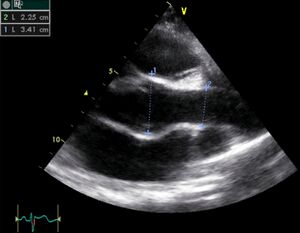

Severe Hypertrophic Cardiomyopathy (HCM)

Case description: Severe Hypertrophic Cardiomyopathy (HCM)

Courtesy of: A. Windhausen, AMC, The Netherlands

MM0003.gif MM0010.gif

MM0005.jpg